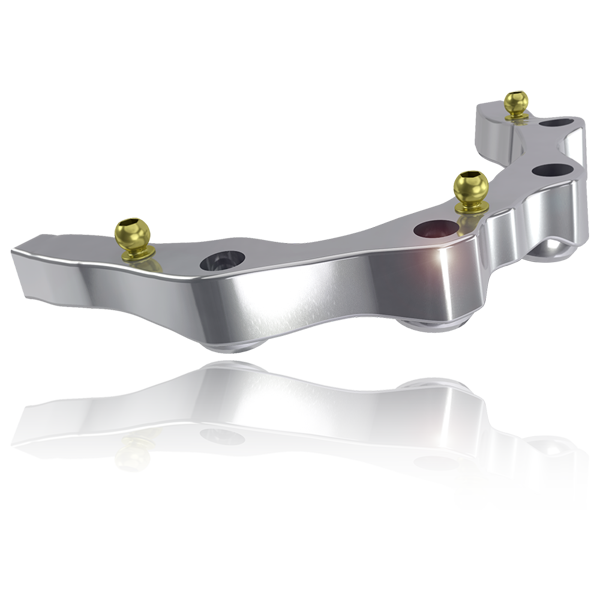

La réhabilitation des mandibules atrophiées représente un challenge majeur en implantologie orale. Des techniques de greffes d’augmentation osseuse verticale ou de transposition du nerf dentaire ont été décrites mais avec des risques post-opératoires significatifs : résorption osseuse, des douleurs sévères ou de la perte de sensibilité (1).

Alternativement, de nombreuses études à 8 ans démontrent qu’il est possible d’obtenir des résultats cliniques aussi bons, voire meilleurs, avec des implants courts comparativement à des implants plus longs placés dans de l’os augmenté (2).